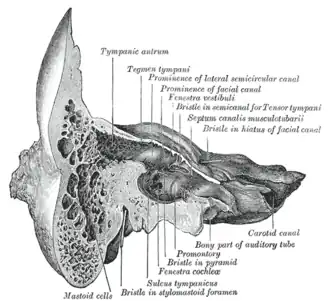

Coronal section of right temporal bone. (Mastoid cells labeled at bottom left.) | |

The mastoid cells (also called air cells of Lenoir or mastoid cells of Lenoir) are air-filled cavities within the mastoid process of the temporal bone of the cranium. The mastoid cells are a form of skeletal pneumaticity. Infection in these cells is called mastoiditis.

Anatomy

The mastoid air cells vary greatly in number, shape, and size; they may be extensive or minimal or even absent.[1]: 746

The cells are typically interconnected and their walls lined by mucosa that is continuous with that of the mastoid antrum and tympanic cavity.[1]: 746

Extent

They may excavate the mastoid process to its tip, and be separated from the posterior cranial fossa and sigmoid sinus by a mere slip of bone or not at all. They may extend into the squamous part of temporal bone, petrous part of the temporal bone zygomatic process of temporal bone, and - rarely - the jugular process of occipital bone; they may thus come to adjoin many important structures (including the bony labyrinth, tympanic cavity, external acoustic meatus, pharyngotympanic tube, superior jugular bulb, posterior cranial fossa, middle cranial fossa, carotid canal, abducens nerve, sigmoid sinus) to which they may disseminate infection in case of infective mastoiditis.[1]: 746